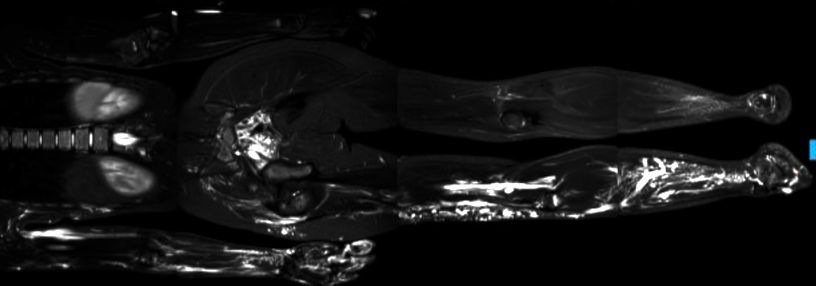

Bambina nata a termine da taglio cesareo programmato per riscontro, alla RM fetale, di linfangioma cistico dell’emisoma destro. Genitori non consanguinei, in anamnesi familiare non patologie di rilievo. Nei primi mesi di vita effettua accertamenti radiologici ed endoscopici che evidenziano la presenza di malformazioni vascolari multiple a basso flusso di tipo misto, capillaro-veno-linfatiche, che coinvolgono: arto superiore destro, con segni di assottigliamento osseo a livello dell’avambraccio e delle falangi distali del secondo e terzo dito; regione mammaria destra; arto inferiore destro; muscolo grande dorsale; muscoli grande, medio e piccolo gluteo; regione vulvare. In regione addominale si riscontrano: ampio collettore venoso esteso dalla regione portale al plesso venoso emorroidario, ectasia delle vene iliache e periuterine, angectasie a livello duodenale e colico (Figura 1).

L’angio-RM cerebrale esclude la presenza di malformazioni vascolari in questa sede. A partire dai 3 anni di vita viene sottoposta a molteplici procedure endovascolari e chirurgiche, perlopiù demolitive: laserterapia, scleroembolizzazione e legatura della vena safena di destra; multipli tentativi di rimodellamento del terzo dito della mano destra, asportazione della vena basilica displastica al polso destro e legatura a livello del braccio destro. Tuttavia i ripetuti interventi eseguiti apportano scarso beneficio alla qualità di vita della bambina, che riferisce persistenza del dolore, soprattutto mattutino, peggioramento del turgore della lesione e della limitazione funzionale della mano destra. Le indagini genetiche sul tessuto asportato mostrano la presenza in eterozigosi a mosaico del 2,5% di mutazione somatica del gene PIK3CA: E545K (c.1633G>A; p.Glu545Lys), quadro compatibile con sindrome da iperaccrescimento PIK3CA-correlata (PROS). Alla luce delle evidenze scientifiche esistenti, viene avviata terapia off-label con sirolimus al dosaggio di 1 mg/m2 al giorno, con regolare monitoraggio dei livelli ematici. A due mesi dall’inizio della terapia si assiste alla scomparsa della sintomatologia algica e al miglioramento dei movimenti fini della mano destra, con netta riduzione dell’estensione e del turgore delle lesioni agli arti, reperti confermati anche alla RM di controllo. La terapia è inoltre ben tollerata dalla piccola, non si sono presentati eventi infettivi secondari né alterazioni degli esami ematochimici.